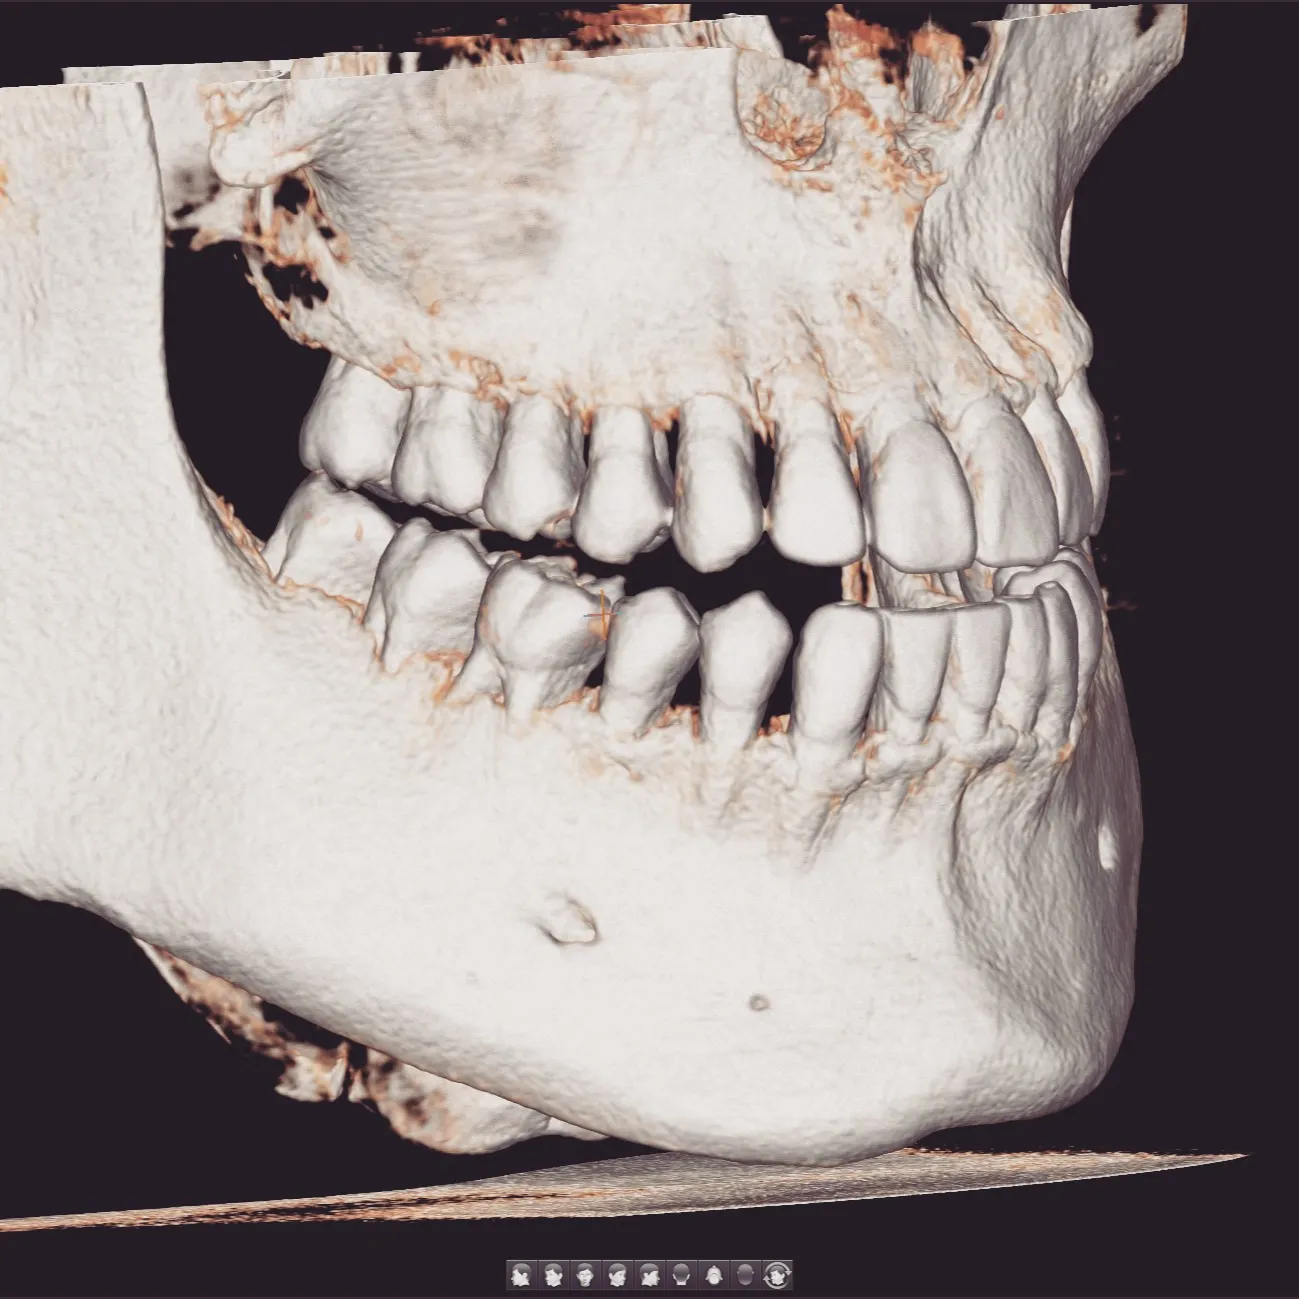

当院ではCBCT(歯科用CT)を導入しており、歯のことを立体的・多角的に把握することができます✨

投稿の写真は院長・私自身のCBCT画像です🙋♂️

こんなにリアルに、立体的に把握できるんです。